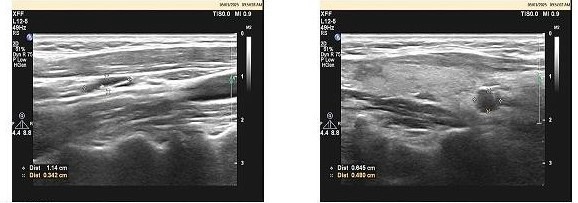

经过多方打听和慎重考虑,孙女士慕名来到了武汉大学人民医院乳腺甲状腺外科陈创教授团队李智宇医生的诊室。当超声科吴田医生为她再度检查时,却发现其双侧甲状腺多发结节:右侧腹侧边缘最大直径0.9cm结节高度怀疑恶变,左侧一直径0.3cm结节也高度怀疑有风险,而右侧颈Ⅲ、Ⅳ区淋巴结的钙化灶,更是一道危险的预警信号。

(右侧腹侧及左侧甲状腺结节)

右侧颈部Ⅲ区、V区淋巴结结构异常(Ⅲ区一个伴钙化)